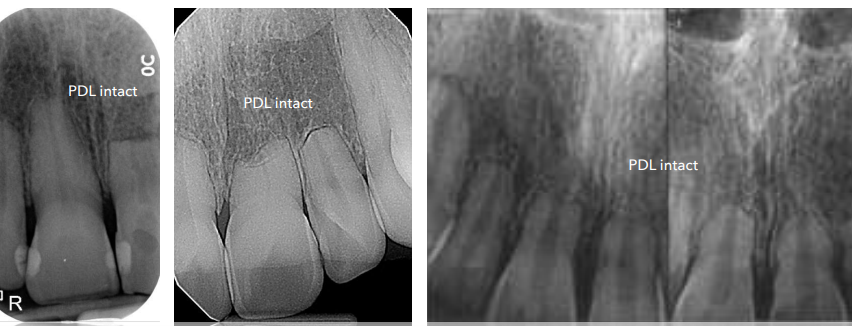

**PDL intact, no PA radiolucency **– no need for endo (used to preserve pulp, tx periradicular disease)

PDL intact, no PA radiolucency

no need for endo